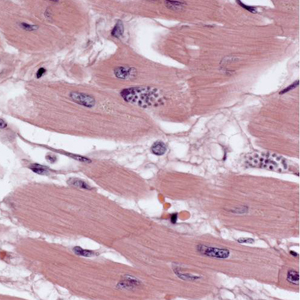

A 27-year-old patient underwent chemotherapy and a bone marrow transplant after being diagnosed with leukemia. Approximately two months after the bone marrow transplant, the patient was admitted to the hospital. The patient presented with severe, intractable cardiac decompensation and died while at the hospital. Autopsy specimens of the heart were sent to Pathology for routine sectioning and staining with hematoxylin and eosin (H&E). Figures A–D show what was observed by the attending pathologist on H&E-stained heart tissue. The slides and a tissue block were forwarded to the CDC’s Infectious Diseases Pathology Branch (IDPB) for further assistance. Specimens taken from the tissue block were also processed and examined by electron microscopy (Figures E and F) by IDPB and the DPDx Team. What is your diagnosis? Based on what criteria?

Figure A